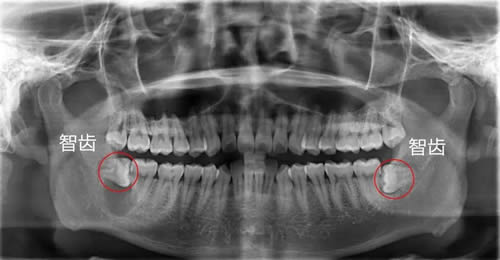

3不正常生长的智齿是什么样?

不正常生长的智齿有:横着的,斜向前的,斜向后的等等奇形怪状都有。

如下图:

斜着长的智齿